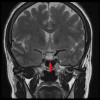

Penanganan seperti apa untuk menurunkan kadar hormon prolactin dan mengecilkan prolactinom pada kasus hiperprolaktinemia

selamat malam dok, izin bertanya terapi bromokriptin pada kasus hiperprolaktinemia, apakah diperbolehkan diberikan untuk terapi hiperprolaktinemia apabila yg sebelumnya menggunakan terapi cabergoline secara rutin? kondisi tersebut menjadi pertimbangan karena cabergolin cukup sulit didapatkan. apabila diperbolehkan bagaimana pengaturan dosis bromokriptin pada kondisi tersebut. mohon solusi nya dokter terimakasih.